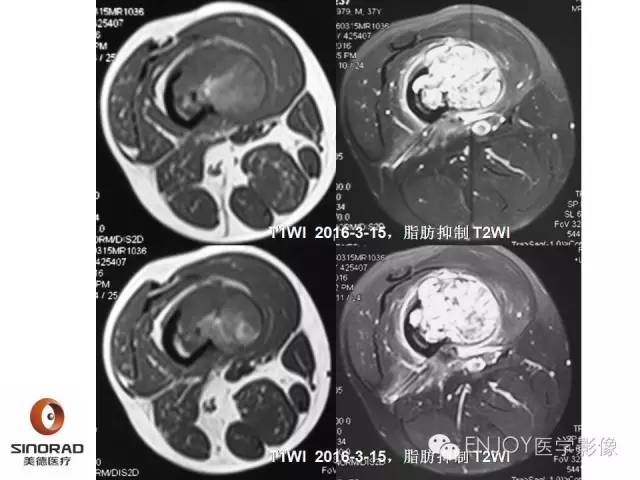

【病例】右侧股骨多形性肉瘤1例X线及MR影像表现

多形性肉瘤(以往称为:恶性纤维组织细胞瘤)